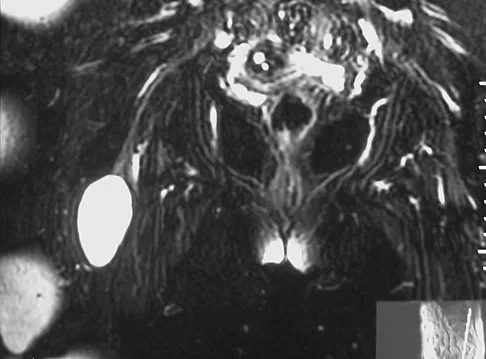

A patient has right shoulder pain. Figure 1a shows a gadolinium-enhanced transverse MRI scan at the level of the coracoid. Figure 1b shows an arthroscopic view of the anterior structures from a posterior portal. These images reveal which of the following findings?

The area shown in the arthroscopic view and MRI scan is referred to as a Buford complex and represents a normal labral variant. It consists of a thickened, cord-like middle glenohumeral ligament, a superior labral attachment of the middle glenohumeral ligament just anterior to the biceps tendon, and absence of the anterosuperior labrum. This combination of findings can be confusing and may simulate labral pathology. Mistaken repair of the lesion back to the glenoid rim can result in significant loss of external rotation. A Bankart lesion would be located at the inferior anterior glenoid rim. The subscapularis is seen anterior to the labrum. Normal variations that occur in the anterosuperior labrum can simulate pathology. Gusmer PB, Potter HG, Schatz JA, et al: Labral injuries: Accuracy of detection with unenhanced MR imaging of the shoulder. Radiology 1996;200:519-524. Griffin LY (ed): Orthopaedic Knowledge Update: Sports Medicine. Rosemont, IL, American Academy of Orthopaedic Surgeons, 1994, pp 47-63.

- Williams MM, Snyder SJ, Buford D Jr: The Buford complex: The "cord-like" middle glenohumeral ligament and absent anterosuperior labrum complex. A normal anatomic capsulolabral variant. Arthroscopy 1994;10:241-247.